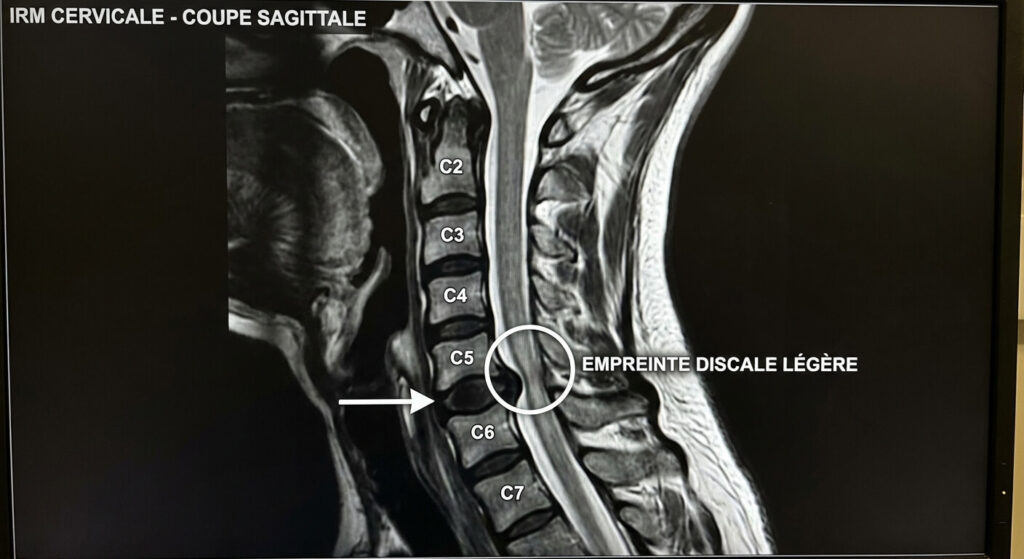

Entre chaque vertèbre se trouve un amortisseur souple : le disque intervertébral. Au fil des années, sous le poids du corps et la répétition des mouvements, ces disques s’usent, s’affaissent et peuvent bomber vers l’arrière, en direction du canal. Lorsque ce bombement discal (ou une excroissance osseuse liée à l’arthrose) dépasse sa frontière naturelle, il vient d’abord chasser le liquide protecteur, puis finit par toucher la surface de la moelle épinière. L’IRM fige cette image : l’obstacle dessine une « empreinte » sur le cordon, modifiant légèrement son contour habituellement parfaitement rectiligne.

| Empreinte sur le cordon médullaire | L’obstacle touche et déforme légèrement la moelle. | Souvent asymptomatique ou légers fourmillements. |